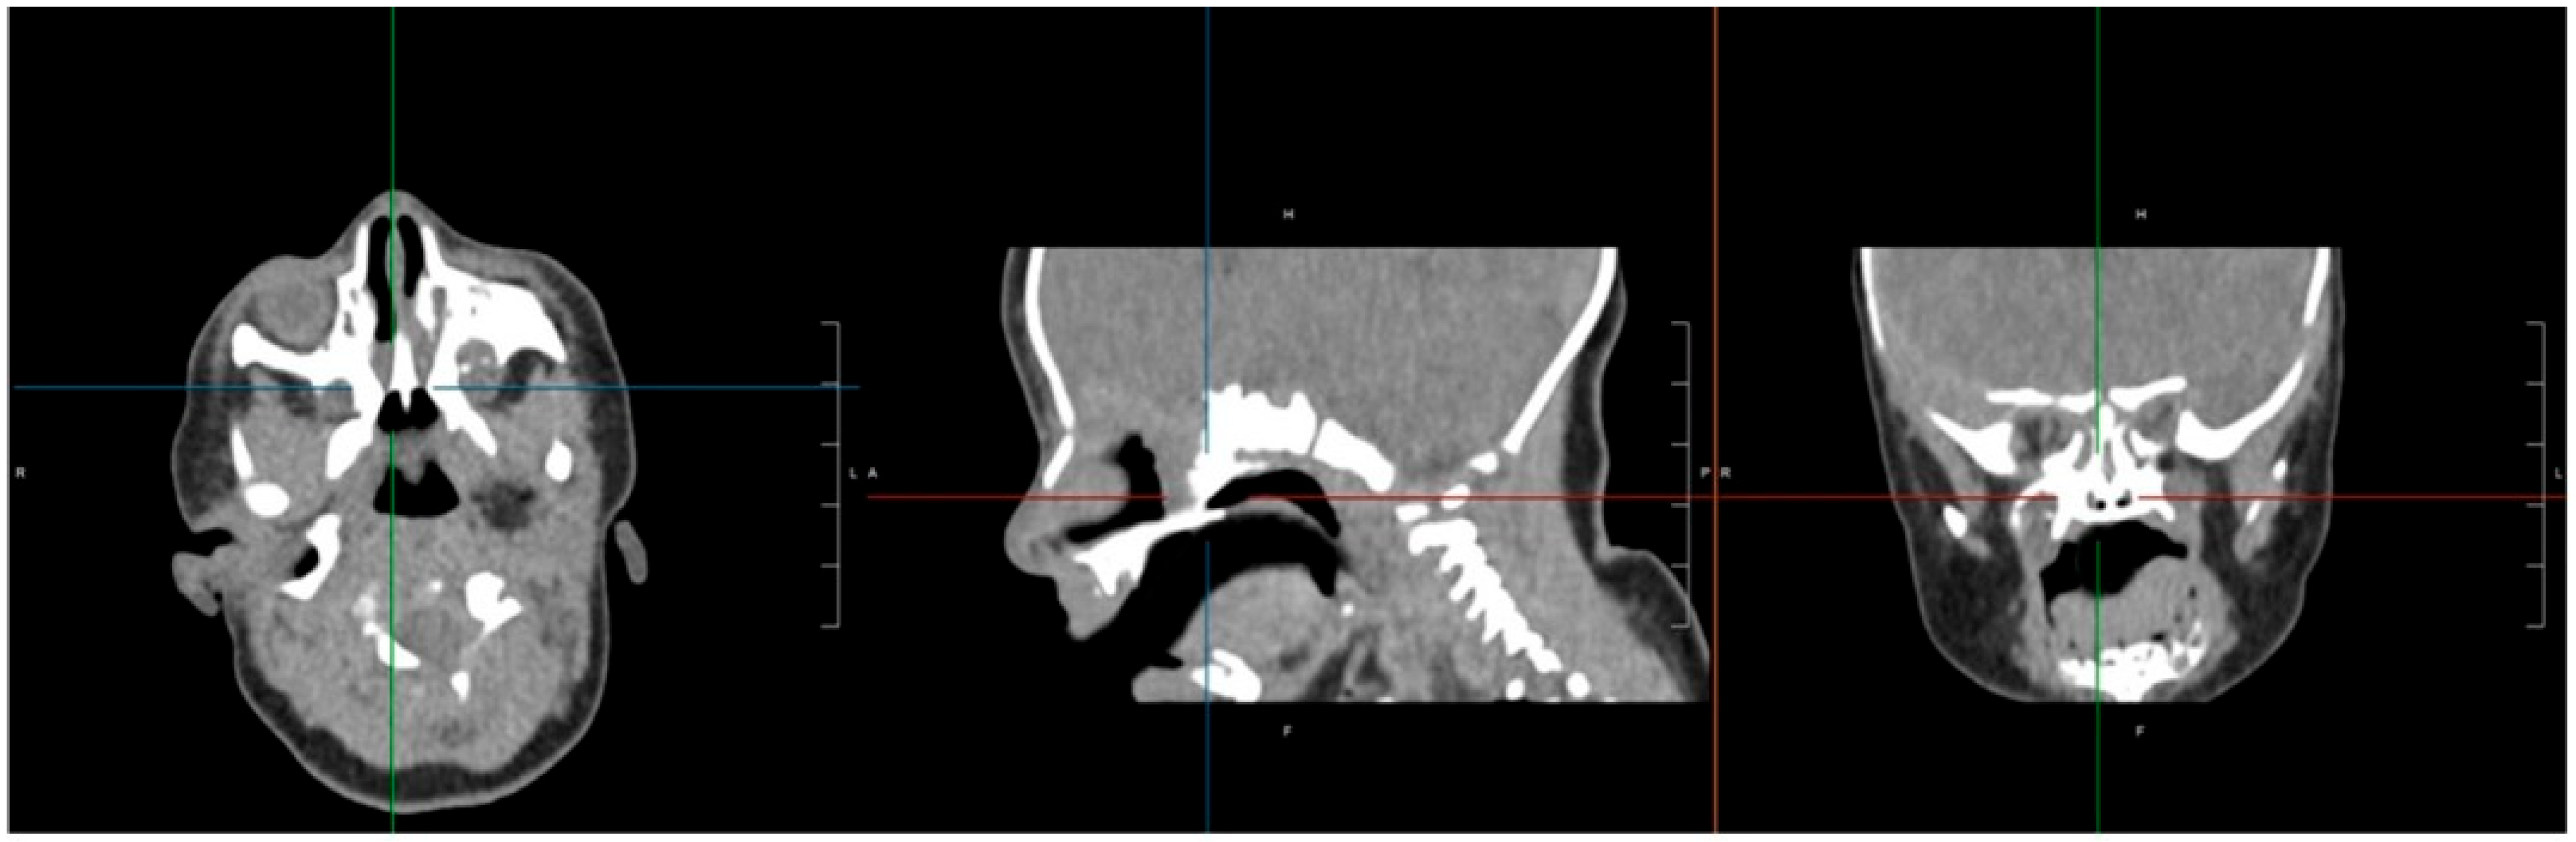

CT imaging confirmed bilateral choanal atresia, as demonstrated by the interruption of the air column on both sides. No bony abnormalities were detected, and the observed membranous appearance was attributed to incomplete physiological ossification of the planum ethmoidalis (Figure 1).

Figure 1. Skull CT highlights the presence of a bilateral membranous septum involving both choanae. The air column was interrupted on both sides; no bone changes were detectable, normal membranous appearance was due to incomplete physiological ossification of the planum ethmoidalis. There was no ethmoidal encephalocele. L: Left; R: right.